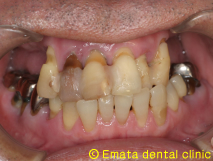

現在世界で最もインプラント治療を手がけているポルトガルのP.マロ先生よりAll-on-4(オールオンフォー)と呼ばれるコンセプトが提唱されました。

All-on-4(オールオンフォー)とは従来のインプラント治療に大きな変革をもたらす、画期的で最新の治療方法です。たった4本から6本でインプラントで12本分の歯を支えることを可能で手術が終わったとたんに入れ歯から開放され、固定式の歯がはいります。

では治療例をみてみましょう。

| All-on-4は4本ではないかとおもいますが、骨の状態や対合歯が自分の歯なのでより確実性をもたせたいため5本で立ち上げ、2本はスリープさせました。

この症例のポイントは、ソケットリフト部位への即時負荷でしょう。アダプテーションテクニックにより40ニュートンの初期固定がえられました(専門的になってしまいましたね)。 麻酔専門医の先生が静脈内鎮静法を行っていますので患者さんは半分寝ているうちに手術が終わってしまいます。 |